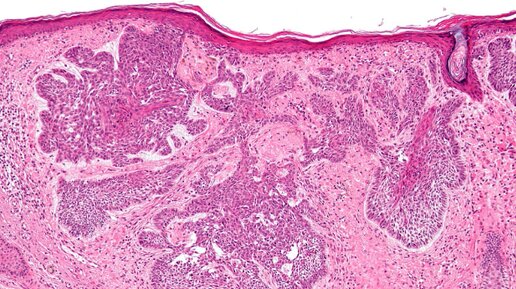

Базалиома (базальноклеточный рак) – наиболее часто встречающаяся (в 80% случаев) злокачественная опухоль кожи. Базалиома может возникнуть на любом участке кожи, но излюбленными являются открытые локализации, подверженные воздействию ультрафиолетового излучения. Прогноз у пациентов с базалиомой благоприятный, поскольку опухоль медленно прогрессирует, а частота метастазирования базалиомы составляет всего 0,5%. В то же время риск местного рецидива базалиомы достаточно высок, достигая 40%. Повышенный...

Зачастую пациенты путают разные кожные новообразования, такие как базалиома и кератома, поскольку они могут выглядеть схоже. Но важно уметь отличить их, так как подходы к лечению этих состояний отличаются. Недавно я провел опрос, чтобы узнать, как часто люди ошибаются в таких случаях, и рад сообщить, что большинство участников верно распознало базалиому. Давайте разберем основные признаки этих образований и поговорим о том, почему важно вовремя обращаться ко врачу. Базалиома или базально-клеточный рак — это одно из самых частых онкологических заболеваний кожи...